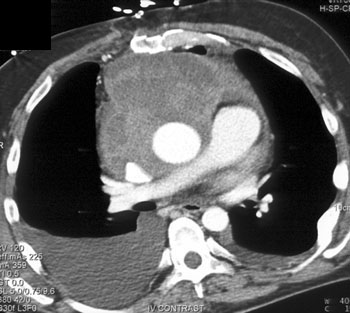

Question 6: 50ish yr old male with increasing SOB and dyspnea.What’s the diagnosis?

Diagnosis: Angiosarcoma of the Pericardium

• Most common cardiac sarcoma

• Most common in middle aged men

• Most commonly located near right atrial free wall with involvement of pericardium

• Typically infiltrates pericardium